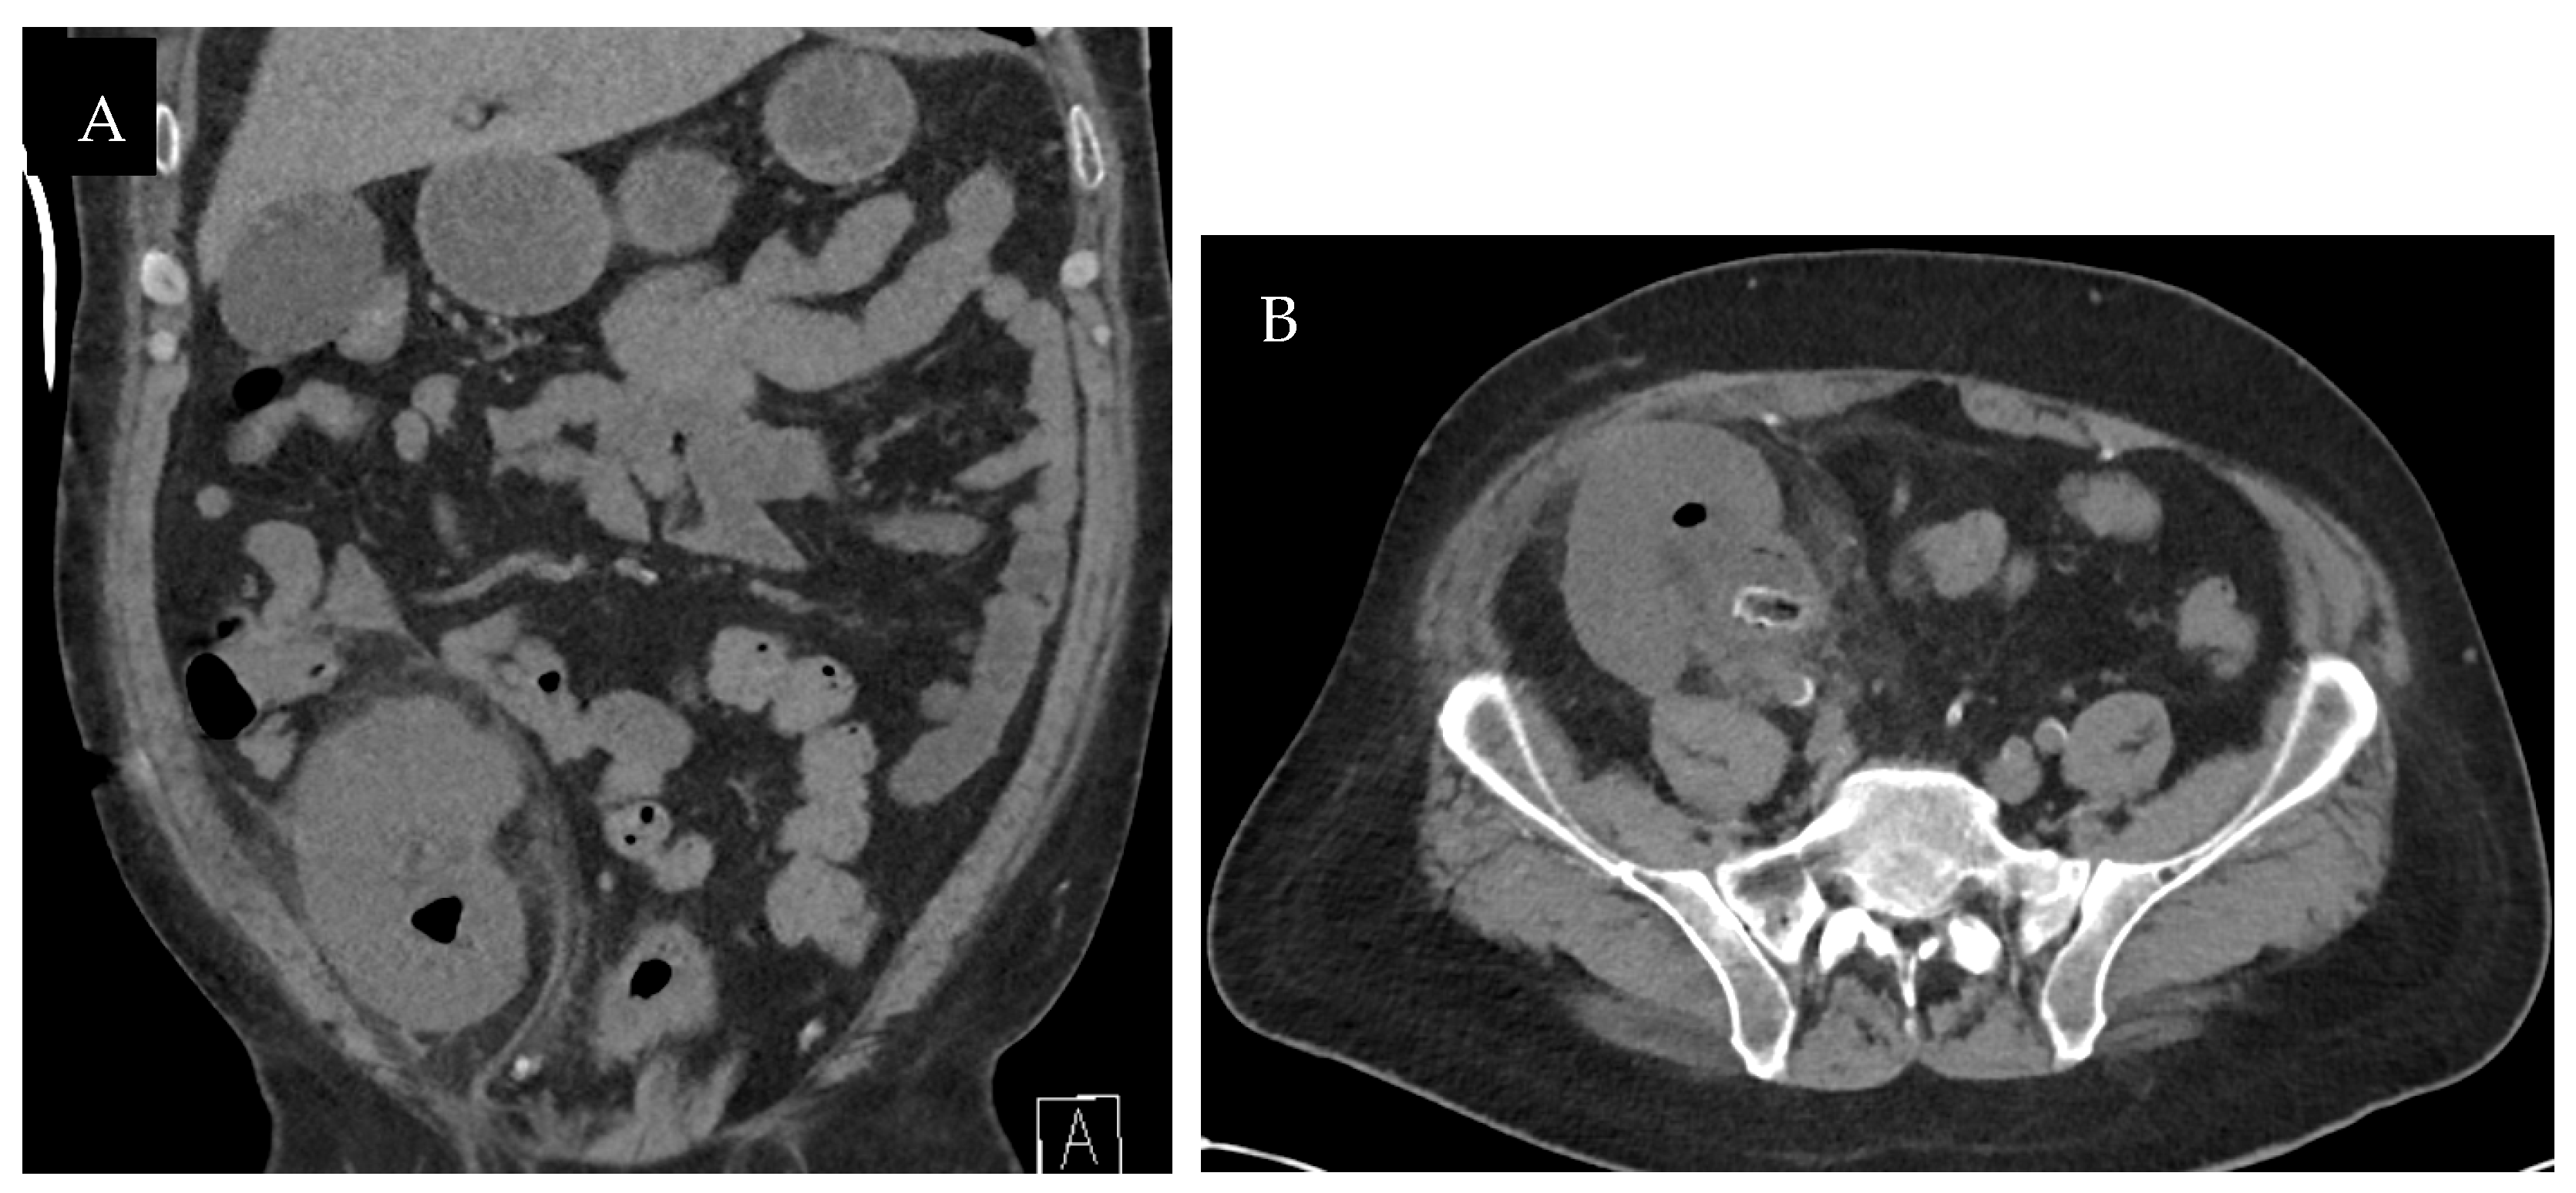

The CT scan without contrast was repeated on post-operative day 6, which demonstrated dense dilatation of the renal collecting system and appropriate positioning of the ureteral stent (Figure 2). His urine output subsequently decreased—producing approximately 150 mL in 24 h. A repeat ultrasound demonstrated a dilated renal pelvicalyceal system containing echogenic debris (Figure 3), so the decision was made to remove the ureteral stent due to likely occlusion on post-operative day 8. Upon manipulation and removal of the stent, a large amount of old blood sediment immediately drained from the ureteral orifice. Urine output improved significantly after stent removal with resolution of hematuria. On post-operative day 10, renal function continued to improve: creatinine 4.3 mg/dL and eGFR 15 mL/min/1.73 m2. He was discharged and scheduled for close outpatient follow-up.

Figure 2. Coronal image from CT scan without contrast demonstrated dense dilatation of the renal collecting system and appropriate positioning of the ureteral stent after repositioning.

Figure 5. One-year post-transplantation non-contrast CT coronal (A) and axial (B) images demonstrated an irregular soft-tissue density with rim calcification at the ureteropelvic junction and proximal ureter measuring 5 × 3.5 centimeters, as well as minimal transplant kidney pelvicaliectasis.